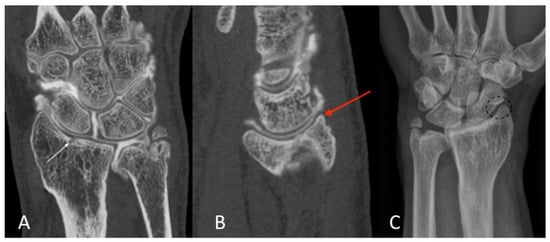

3. Results

The qualitative image analysis was excellent in all CBCT-A cases corresponding to the best scale for image quality, with an excellent inter-observer concordance (kappa = 1), as shown in Figure 4, Figure 6, and Figure 7. Twenty-four patients had an OA diagnosis (KLC ≥ 2) with the CBCT-A, and twenty-one were subclassed with DR. No statistically significant difference was observed in terms of sclerosis (p = 0.29) and erosion (p = 0.184) between both modalities. Examples of OA underestimation, with DR compared with CBCT-A, are shown in Figure 6.

Figure 6. CBCT-A of left wrist in coronal (A) and sagittal (B) planes, which showed sub chondral erosion ((A) white arrow) and definite anterior osteophyte of the radial lip ((B) red arrow), grade 3 of the KLC scoring system. The AP DR showed a possible joint space narrowing between the scaphoid and radial styloid ((C) dark dotted circle), grade 2 of KLC scoring system. The KLC scoring based on DR is underestimated compared to CBCT-A. As osteoarthritis was confirmed between the radius and scaphoid bone surfaces, scaphoidectomy was performed for this patient instead of styloidectomy considered initially based on DR analysis. CBCT-A: cone-beam computed tomography arthrography; DR: digital radiography; KLC: Kellgren and Lawrence classification.